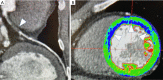

Figure 9

Cardiac computed tomography (CCT) 3D reconstruction of the left coronary artery with plaque components: white arrows indicate calcified elements of the plaque, instead yellow arrows indicate non-calcified ones (A) and fractional flow reserve (FFR) values (B) (SmartFFR, SMARTool platform for CDSS) showing a left anterior descending coronary flow-limiting stenosis with a value of 0.599694.